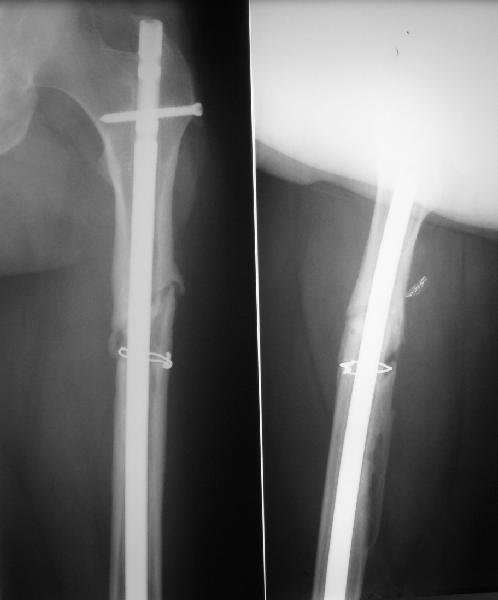

фото несращения бедра